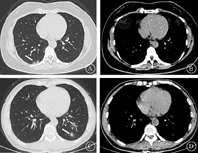

试验组和常规组图像质量均可满足诊断要求(图1),试验组专家1和2主观评分分别为(4.72±0.55)、(4.63±0.58),常规组分别为(4.58±0.56)、(4.60±0.56),差异无统计学意义(P>0.05)。试验组和常规组主观评分一致性检验Kappa值分别为0.804和0.831,说明2位高年资影像专家的图像质量等级评分一致性良好。

注:白色箭头为磨玻璃影